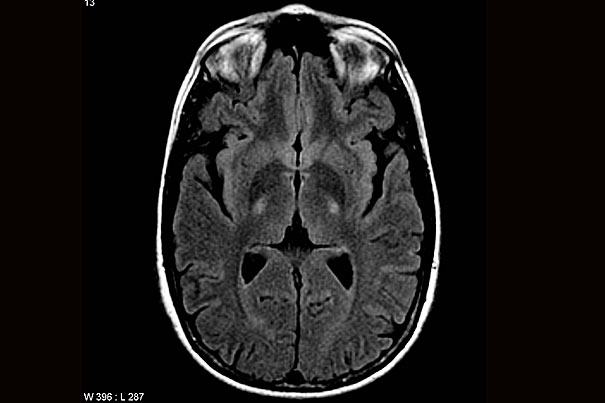

Blood test has potential to detect earliest signals of Alzheimer’s disease

New study suggests higher levels of pTau217 predict a faster progression, even when initial brain scans appear normal